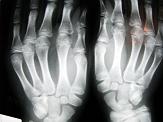

Los rayos X constituyen un salto sorprendente para la medicina, fue descubiertos de manera accidental por el físico alemán Wilhelm Conrad Roentgen. Después, los físicos franceses Pierre y Marie Curie dieron con el radio.

- El descubrimiento de los rayos X y su posterior uso en medicina